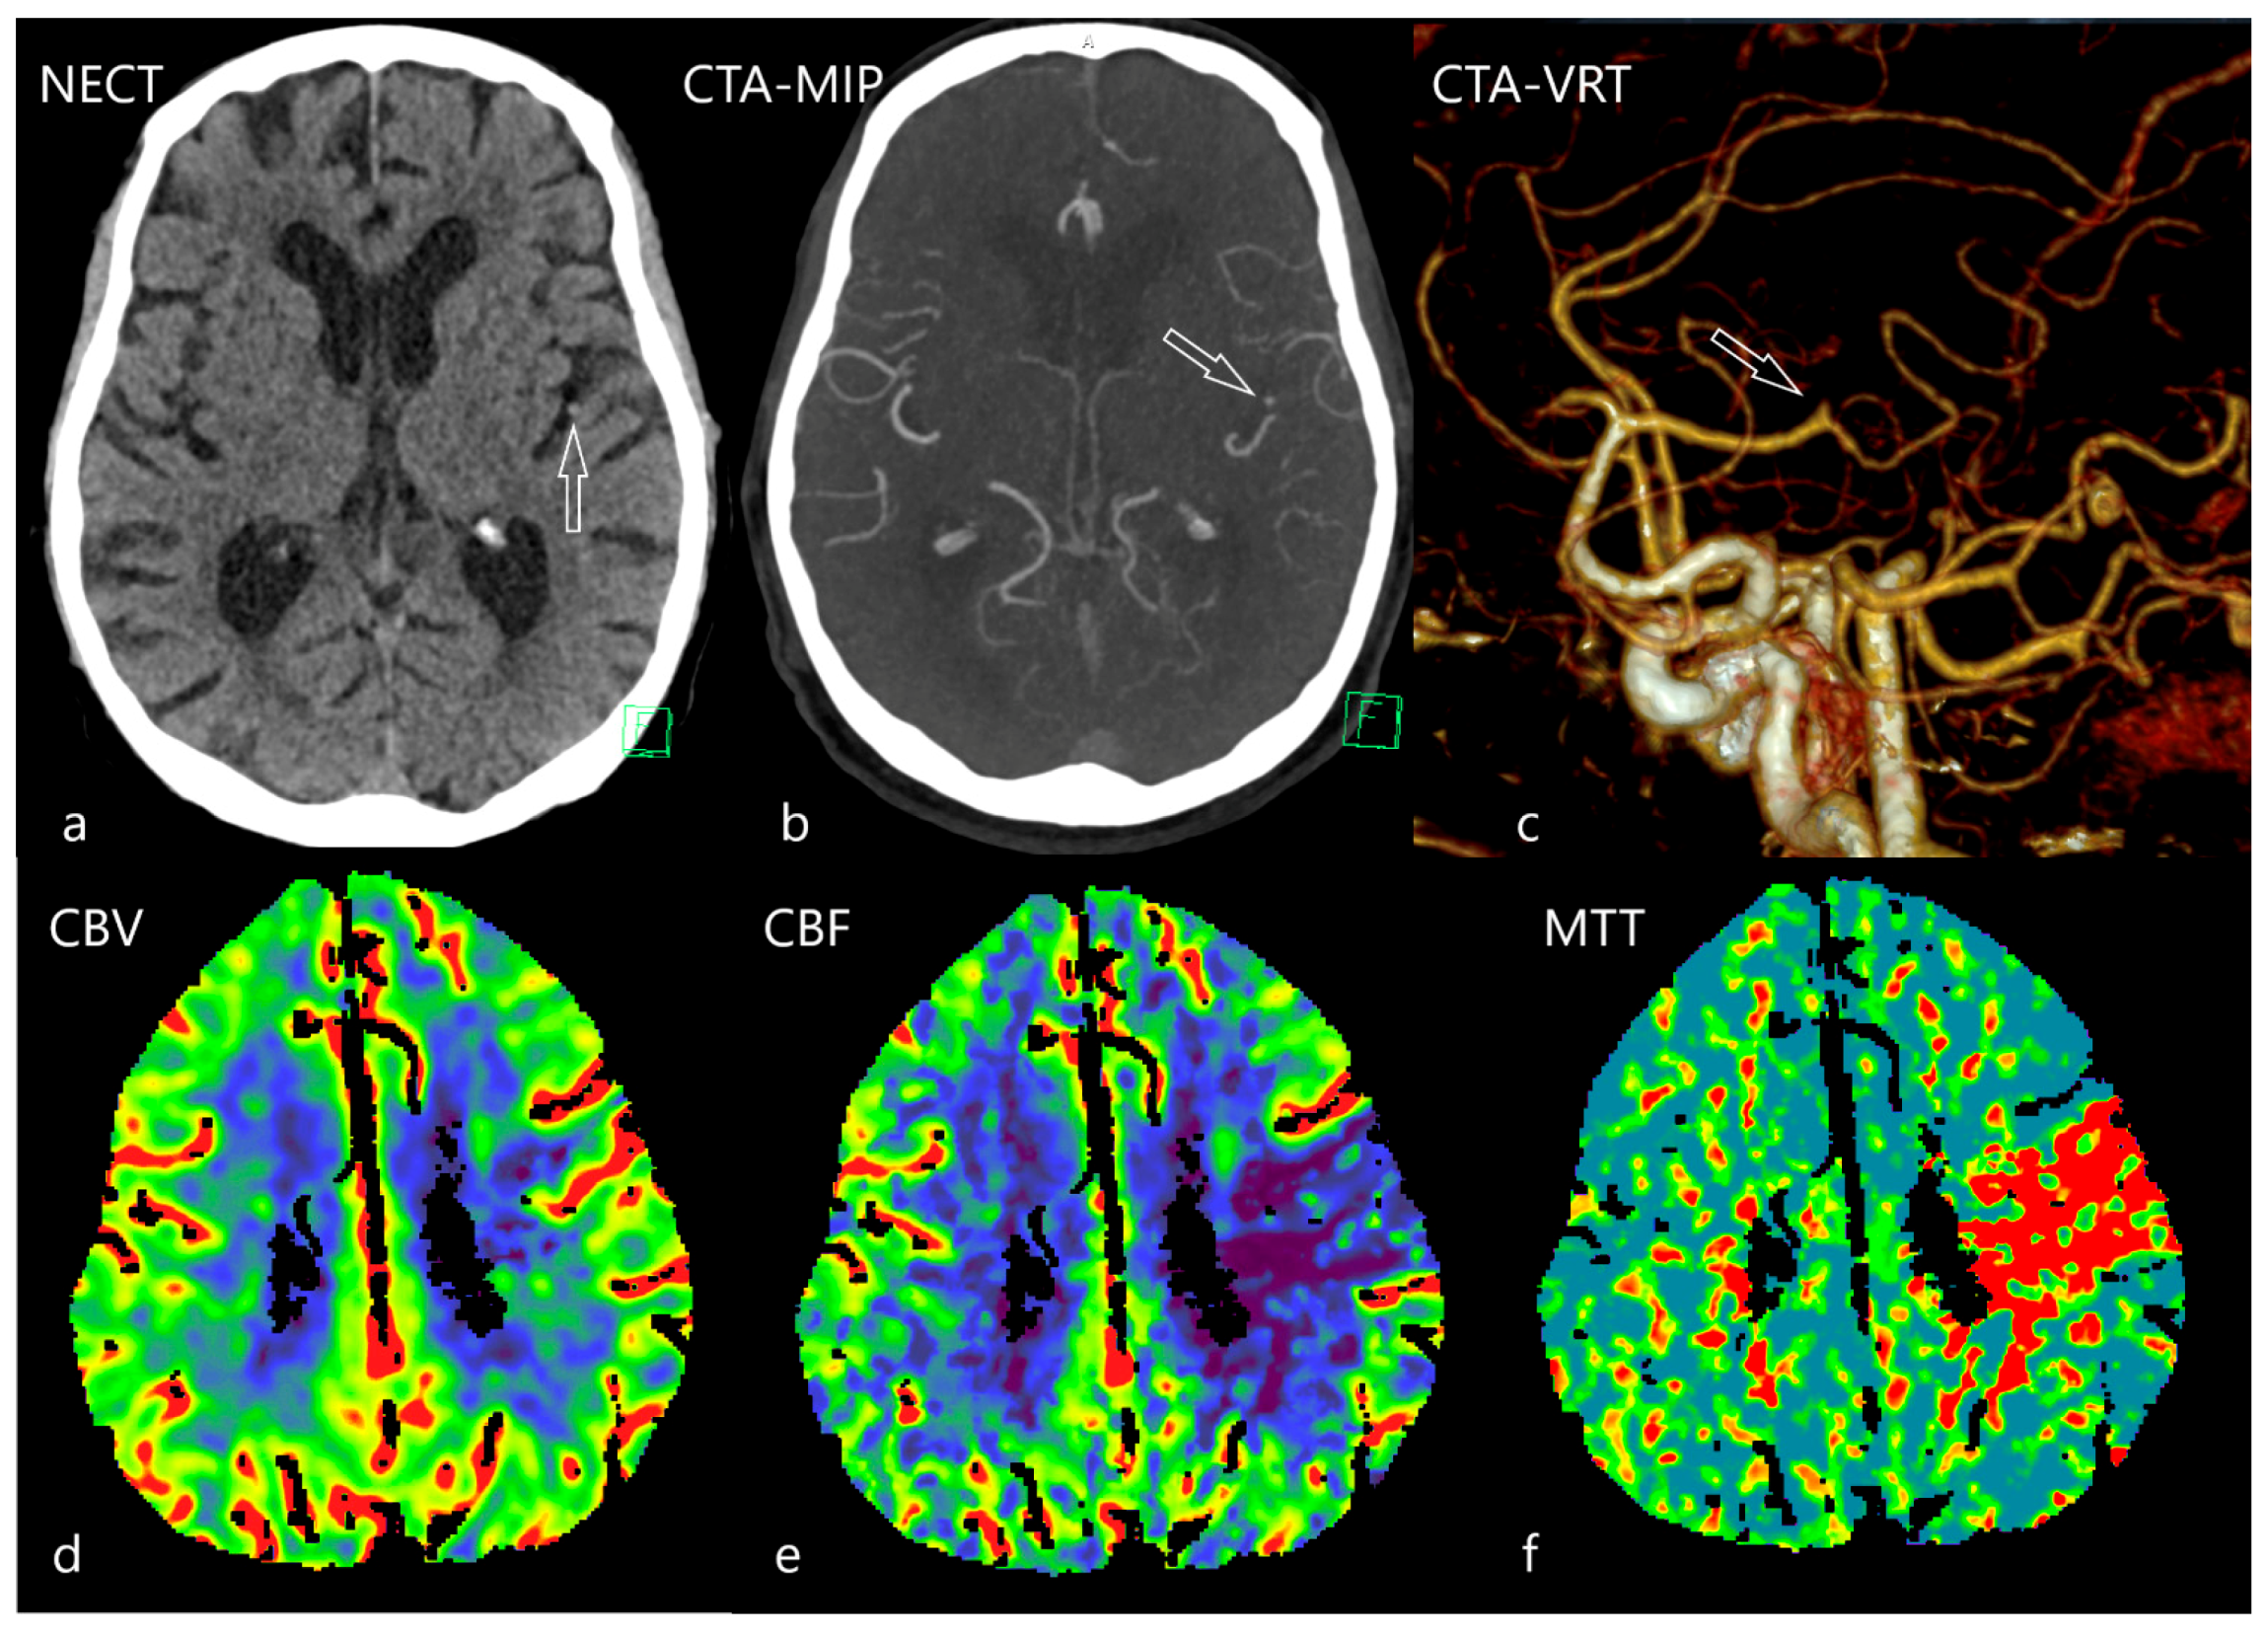

4. Second Task: To Identify Potential Large Vessel Occlusion and Its Localization

5. The Third Task: To Estimate the Ischemic Core

- Kremenova, K.; Holesta, M.; Peisker, T.; Girsa, D.; Weichet, J.; Lukavsky, J.; Malikova, H. Is limited-coverage CT perfusion helpful in treatment decision-making in patients with acute ischemic stroke? Quant. Imaging. Med. Surg. 2020, 10, 1908–1916. [Google Scholar] [CrossRef]